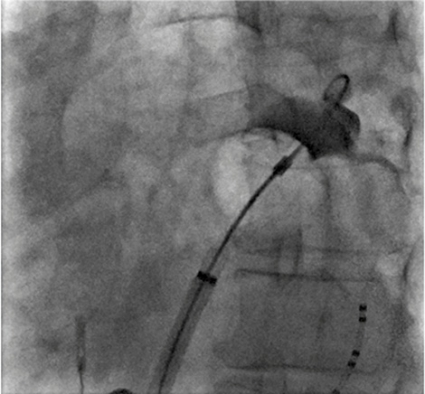

Initialt användes värmeenergi (radiofrekvensablation) punktvis via en kateter mot områden runt lungvenerna för att avlägsna därifrån kommande spontant uppträdande elektrisk aktivitet och därigenom förebygga anfallsvis uppträdande förmaksflimmer [3]. Metoden innefattar punktion av förmaksseptum, s k transseptal punktion. Konventionell röntgengenomlysning i olika projektioner krävs för anatomisk vägledning vid placering av katetrar.

Studier har sedermera visat att elektrisk isolering av samtliga lungvener, lungvensisolering (Figur 3), krävs för att uppnå bästa resultat, vilket i dag är den standardteknik som rekommenderas vid ablation av förmaksflimmer [4]. Vanligen används radiofrekvensenergi, och flera nya katetermodeller har utvecklats och anpassats till lungvenernas anatomi (Figur 3). För att förenkla ingreppet och minska risken för komplikationer har även frysning (kryoablation) med s k kryoballonger utprövats [5].